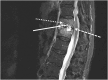

Case presentation: We report a case of a vertebral osteomyelitis caused by carbapenem-resistant Enterobacter cloacae successfully treated with extended-infusion of I-R (1.25 g q6h over 2 h), then with continuous infusion of MVB (2 g q4h as over 4 h). Therapeutic drug monitoring confirmed that extended-infusion of I-R and continuous infusion of MVB achieved serum concentrations up to 12 mg/L of imipenem and 19 mg/L of meropenem, respectively.